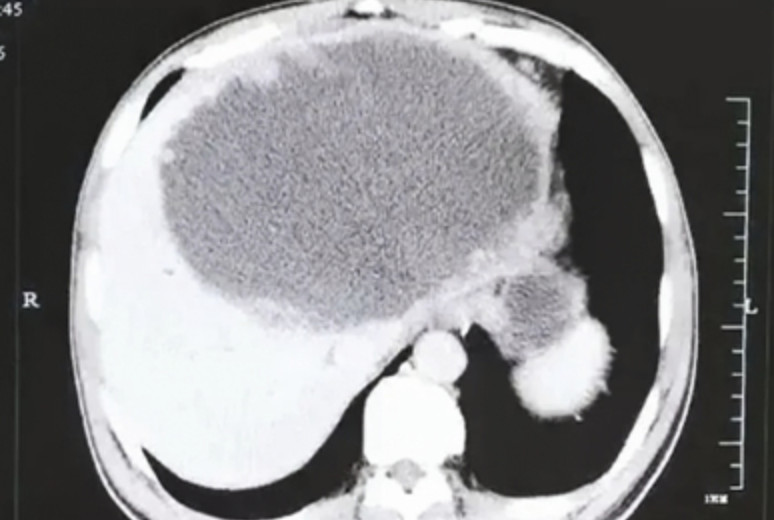

▲男子左肝被掏空长满虫卵。(圖/翻攝自都市快報)

4個月過去了,他一直以為是心情鬱悶所致,直到出現了3天的畏寒、發熱,才到杭州市第一人民醫院肝膽胰外科就診。這一檢查可把醫生和謝男都嚇壞了,檢查顯示:謝男的左肝已經被「掏空」,變成了一個大膿球。

經過多學科會診及討論後,醫生果斷為患者進行了手術,將左半肝切除。誰都沒有想到,醫生切開後看到,膿腫壁上大量的腫瘤樣結構竟然是「肉芽腫性炎性腫塊」,裡面甚至還爬滿了燈泡狀、殼厚的華支睾吸蟲蟲卵(又稱為肝吸蟲),膿腫內多得數不清,看得人頭皮發麻……。